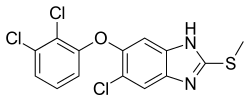

For control of fascioloidosis in wild ruminants, successful application of anthelminthics in feed is necessary. The drug has to have flavour and smell that do not prevent animals from eating medicated feed. In addition, there should adequate therapeutic scope, i.e. span between therapeutic and minimal toxic dose. Therefore, only some of anthelminthics that are efficient in domestic ruminants have been tested in wild ruminants infected with F. magna.[8] Several drugs, namely oxyclozanide, rafoxanide, albendazole, diamphenetide, closantel, clorsulon, and triclabendazole, have been used in control of F. magna infection in cervids. However, the results have differed between different authors. In the same way as for F. hepatica, triclabendazole seems to be the most effective against F. magna.[60] Fascioloidosis of cervids was successfully controlled with triclabendazole in the United States,[61] and triclabendazole with levamizole in Hungary,[16] Canada,[62] Austria,[13] and Croatia.[63] In contrast, rafoxanide is commonly used in treatment in Czech Republic[12] Slovakia[8] and Hungary.[16] Nevertheless, recent studies suggested that use of rafoxanide in control of F. magna infection should be considered.[12] Unfortunately, rafoxanide in a commercial drug called Rafendazol Premix is the only registered drug for wild ruminants. Triclabendazole and others are produced as drugs for domestic animals and it can be used in free-living animals only with special permit. In some cases, it may be difficult to determine if F. magna or a different fluke such as Fasciola hepatica or Fasciola gigantica is causing pathology since all these flukes will have the same clinical signs. In the case that the identity of the trematode cannot be determined, the drug triclabendazole can be used since this will deal with all three parasites.[64]